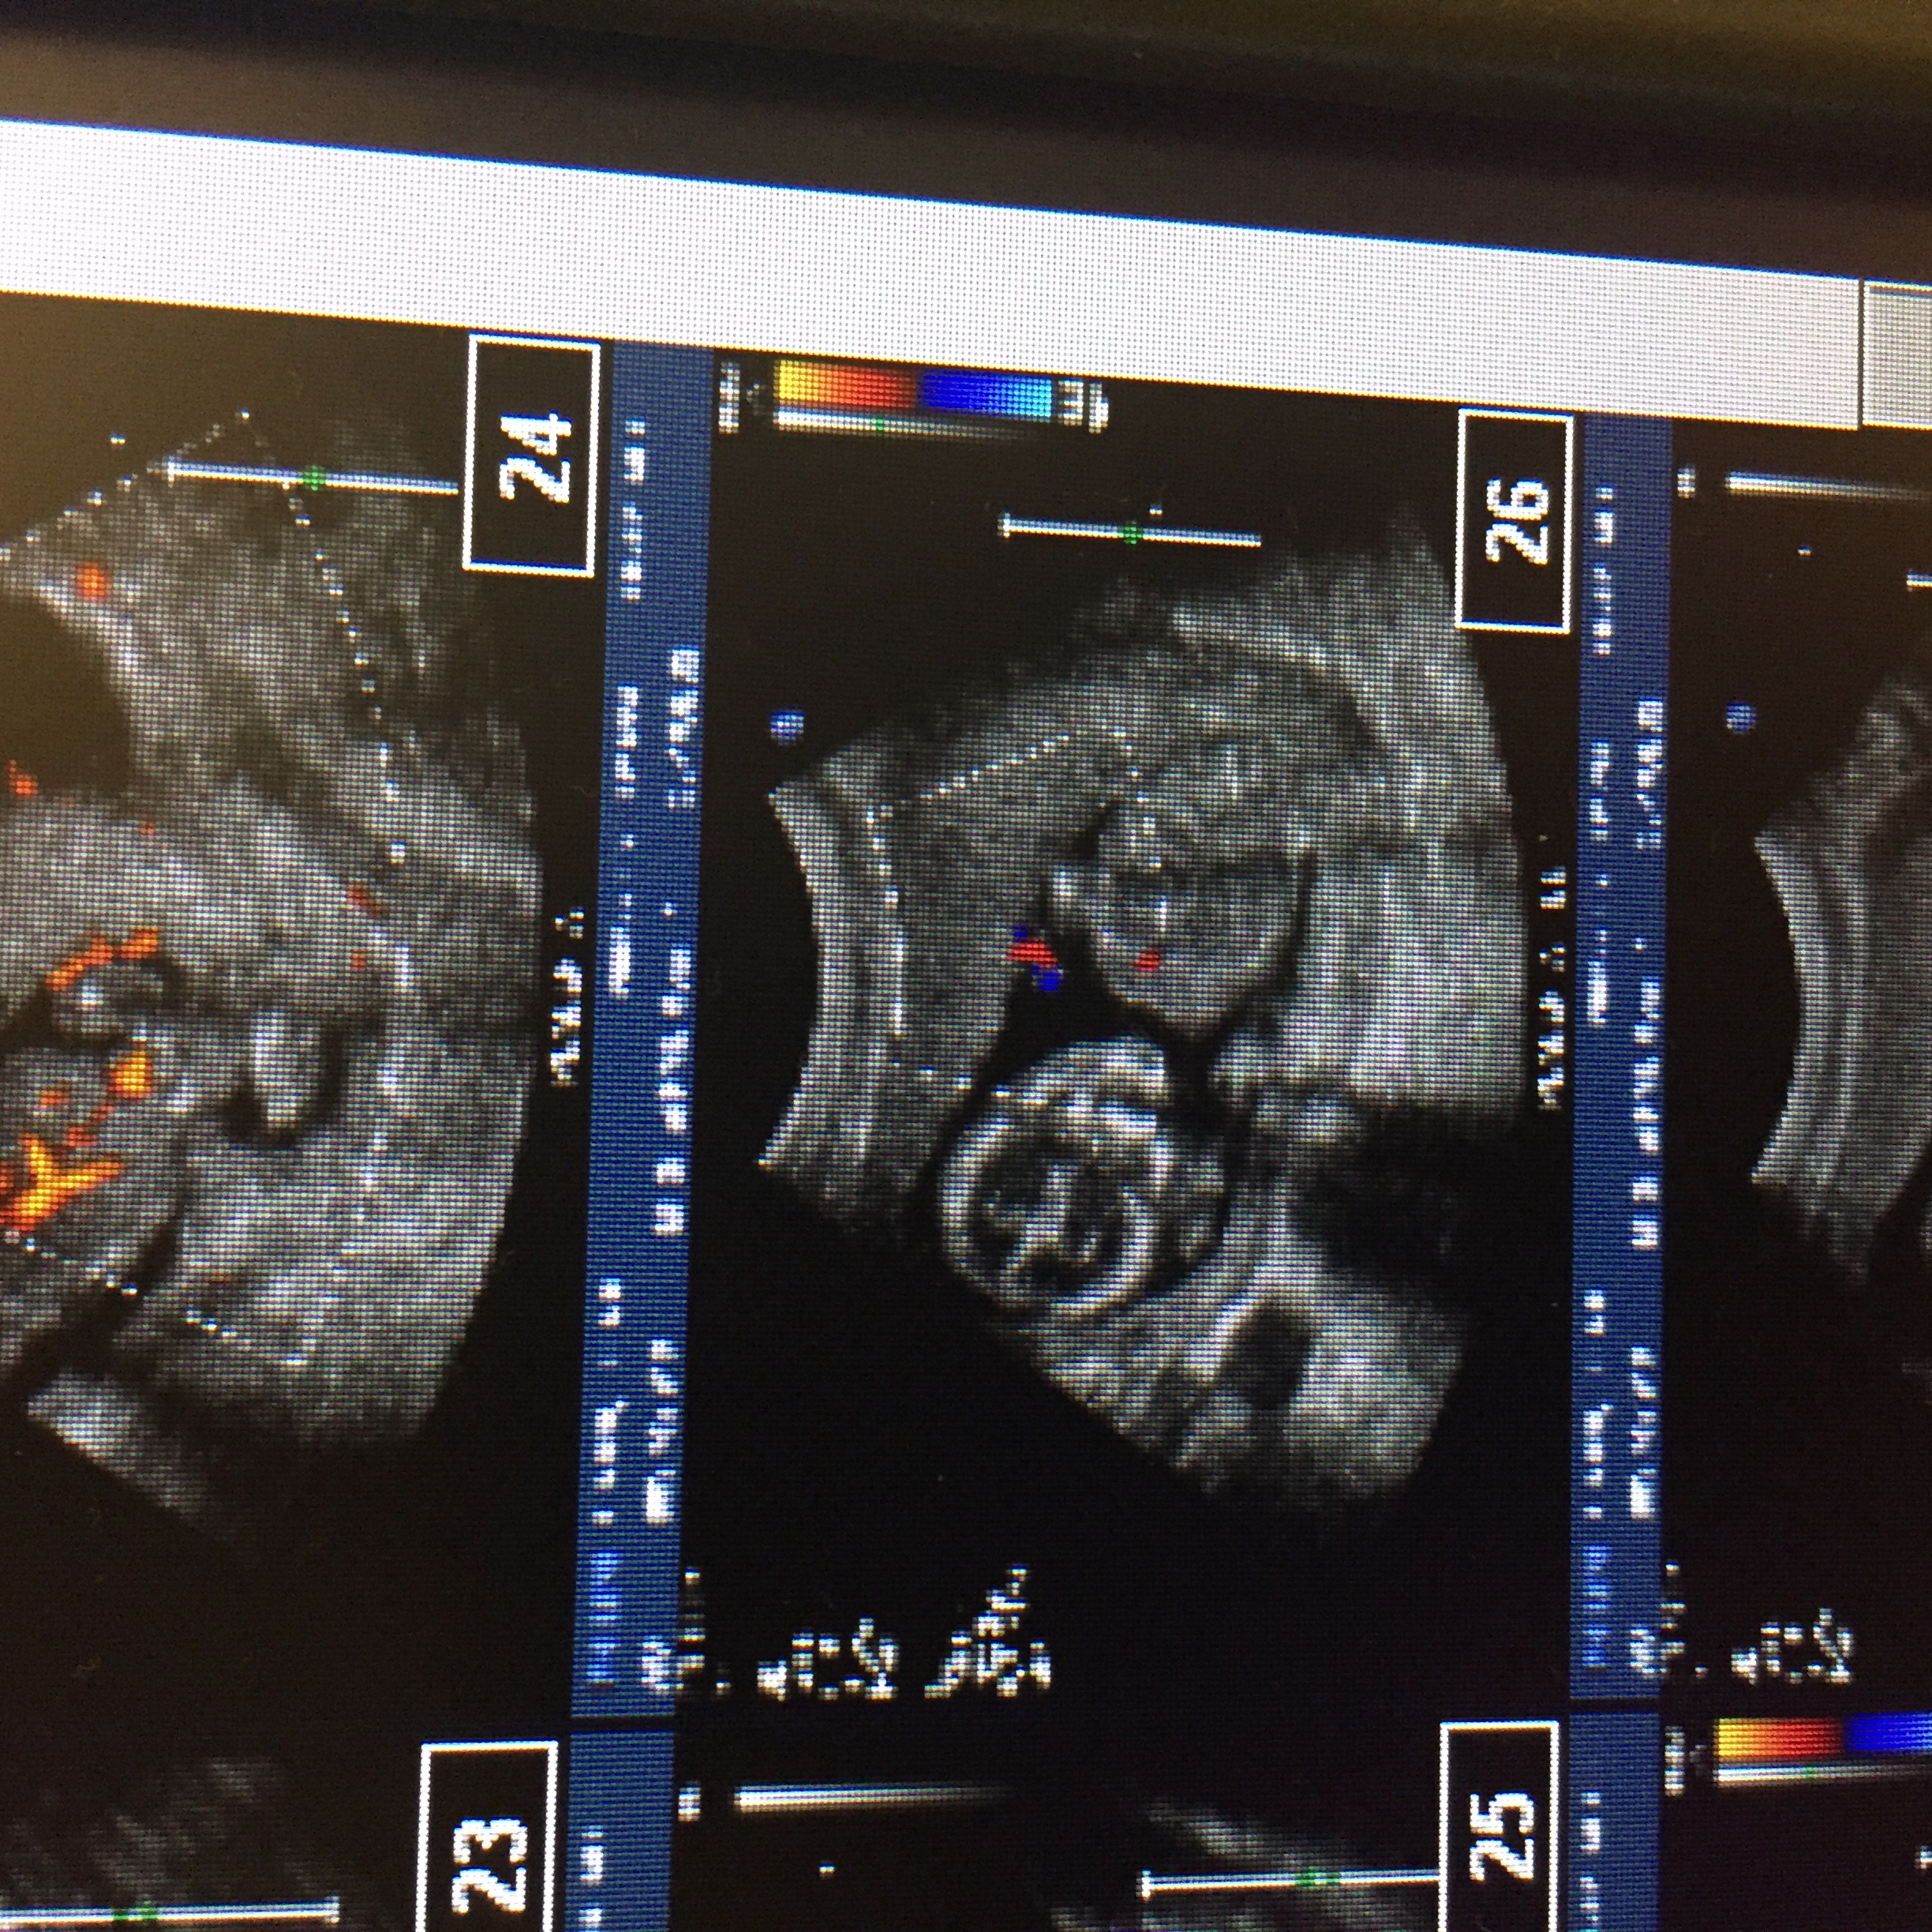

Here is the whole screen shot. On the big picture it looks like the cord is kind of between the legs. The potty shot is the top left one. Still a little change for a girl perhaps.

Attachment 33168

Difficult to tell if it's a penis or cord, but for now I'm leaning boy.

boy lean also